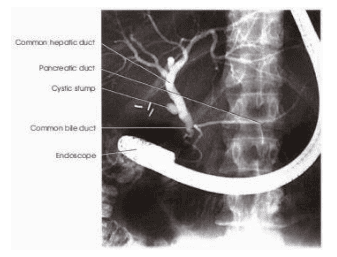

Hình ảnh cây đường mật trong nội soi mật tụy ngược dòng

Hình ảnh X quang của hệ thống đường mật khi túi mật còn, đường kính của đường mật trên X quang không quá 1cm. Một khi túi mật đã cắt, khi bơm chất cản quang thuốc không vào túi mật nên áp lực trong ống mật chủ sẽ cao hơn và đường kính ngang lúc này lớn hơn nhưng không quá 1,3 cm. Hình đường mật trong gan trông giống như ảnh của một nhánh cây khô. Một khi không thấy được ảnh của nhánh gan có thể là dạng xơ gan hoặc do bất thường bẩm sinh ở trẻ em, người lớn ít gặp.

Hình ảnh X quang cây đường mật ở bệnh nhân đã cắt túi mật